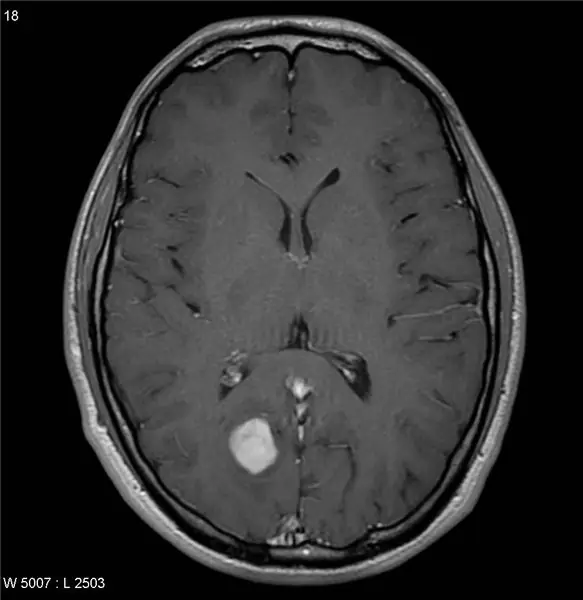

Теперь, когда у нас есть последняя опухоль, мы можем выполнить несколько функций с изображением, чтобы дать несколько более конкретных характеристик. В нашей программе мы хотели рассчитать размер, площадь и расположение опухоли по отношению к общему изображению. Для этого мы смогли использовать некоторые встроенные функции из MatLab, чтобы сделать этот процесс очень простым. Функция regionprops из Matlab позволяет нам вычислить большую часть желаемой информации с помощью всего нескольких строк кода (дополнительная информация здесь: https://www.mathworks.com/help/images/ref/regionp…). расположение и размер относительно изображения и сохранить его в текстовый файл, чтобы сохранить информацию, мы использовали этот код:

% Сохранение результатов в виде текстового файла FileName = 'MRI Brain Tumor Results';

fid = fopen (имя файла, 'вес'); % открывает файл

stats2 = regionprops (BW, 'Центроид', 'Площадь');

center = stats2. Centroid;

[строки, столбцы] = найти (BW);

Hrow = max (ряды); Lrow = min (ряды); rowBounds = [Хроу, Лроу];

Hcol = max (столбцы); Lcol = min (столбцы); colbounds = [Hcol, Lcol];

После использования параметра regionprops для определения местоположения центра опухоли и количества пикселей, которые он заполняет, мы захотели найти область, которую охватывает опухоль. Для этого мы нашли все строки и столбцы, в которых были единицы, затем провели поиск самой высокой и самой низкой строки и столбца, чтобы получить общее пространство, охватываемое опухолью. Чтобы вывести всю эту информацию в командное окно, мы использовали:

fprintf (fid, 'Центр опухоли расположен в координатах (% 0.f,% 0.f) n', center (1), center (2)); fprintf (fid, 'Опухоль опухоли простирается от От% 0.d до% 0.d по оси X и% 0.d и% 0.d по оси Y. / N ', colbounds (2), colbounds (1), rowBounds (2), rowBounds (1));

fprintf (fid, 'Опухоль занимает площадь% 0.d пикселей. / n', stats2. Area)